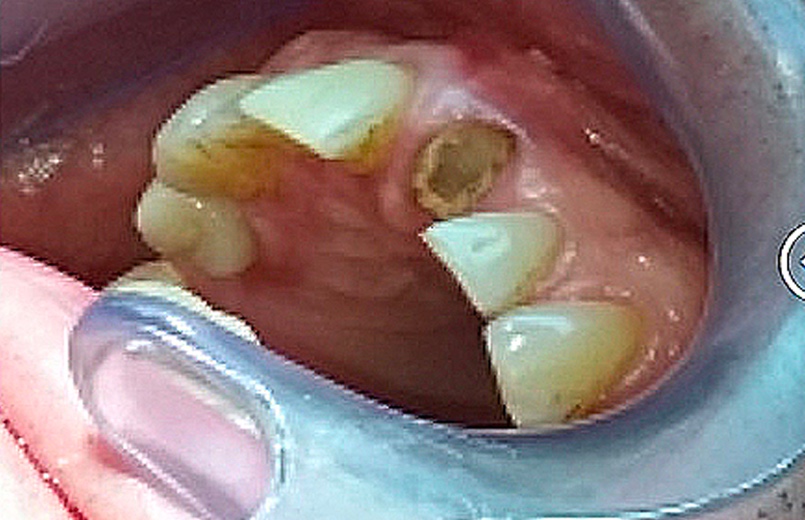

En raison de problèmes de rhizalyse, une résorption pathologique de la racine, ainsi que d’une infection, l’incisive centrale du patient a été extraite.

Lors de cette extraction, des biomatériaux (substituts osseux) ont été utilisés pour combler l’alvéole vidée. Il était également essentiel de réparer ou de renforcer la paroi externe de cette alvéole pour prévenir sa résorption. La finesse de cette paroi autour de la racine naturelle de l’incisive (quelques dixièmes de millimètres) ne permettait pas la pose d’un implant seul, compte tenu du vieillissement des tissus environnants et de l’importance de l’esthétique à ce niveau.